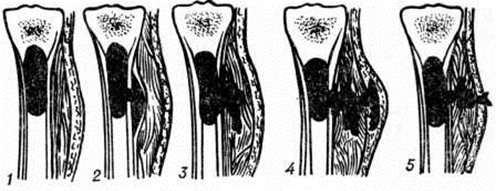

Схема формирования костной полости вокруг костных осколков и инородных тел при огнестрельном остеомиелите: 1 — полость обусловлена расположением осколков; 2 — полость образовалась на месте множественных осколков; 3 — полость образовалась на месте смещения отломков; а — перелом, б — ранние стадии формирования полости, в — поздние стадии хронического огнестрельного остеомиелита (видны сформированные остеомиелитические полости).